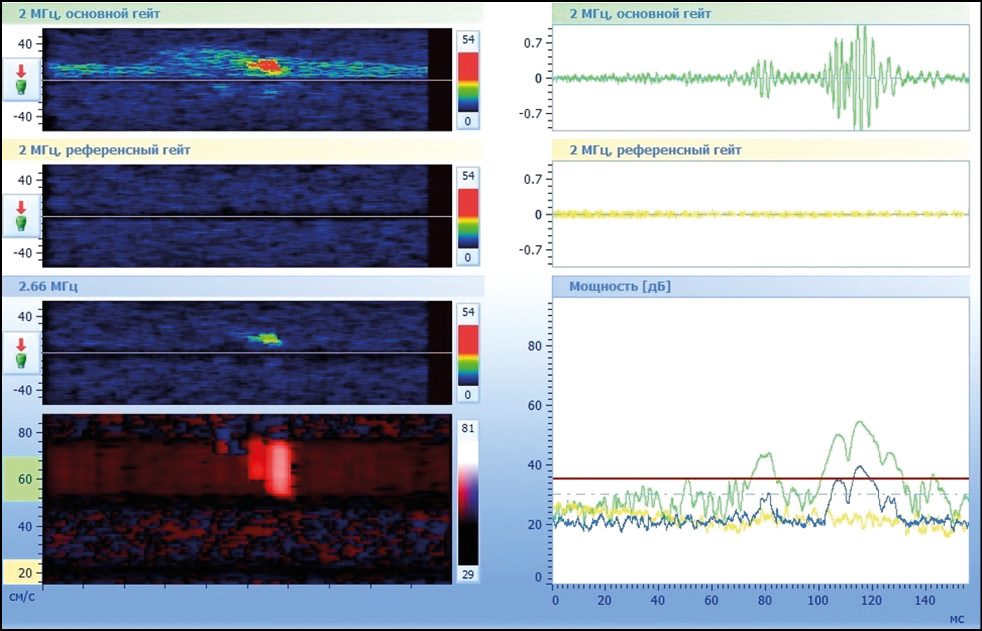

В случае наличия признаков микроэмболии в режиме постобработки мониторинга оценивали интенсивность (количество МЭС в час), для каждого МЭС длительность (мс) — косвенную характеристику размера эмбола, частоту (Гц) — косвенную характеристику структуры эмбола, мощность (дБ) — интегральную характеристику микроэмбола [3]. Пример оценки характеристик МЭС представлен на рис. 1, 2.

Рис. 1. Экспертный анализ амплитуды и мощности сигнала для сортировки микроэмболических сигналов от артефактных сигналов